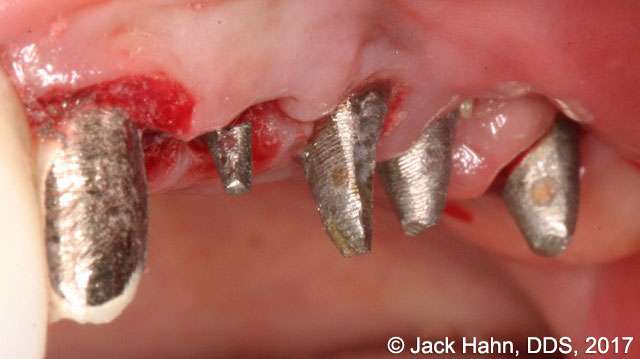

CASE #4 Trauma Case – Central Incisors Internal / External Resorption

Implants, that replace failed endo- or perio-compromised teeth, have a MUCH higher success rate with laser decontamination of the osteotomy site. LightScalpel laser surgical and perio laser tips ensure excellent access to extraction socket for the optimum removal of granulation tissue and socket decontamination (protocol involves manual curettage of the socket with alternating rinsing and lasing).

The patient, a 17-year-old female was involved in a water slide accident 3 years ago. As a result, both central incisors were avulsed and an endodontist replanted them. Both teeth exhibited internal and external resorption. Dr. Hahn extracted both central incisors, removed all the root fragments and sanitized the sites with the LightScalpel laser which also eliminated any granulation tissue. The #8 area was prepared to place a Hahn 4.3×13 Implant and #9 was prepared for a Hahn 3.5×13. 3mm tall Hahn healing abuts were placed slightly below the gingival-tissue level to help develop an emergence profile when at the restoration time in 4 months. Upon seeing the x-ray, Dr. Hahn tightened the healing abutment on #9 to be sure that it was completely seated on the implant. 45nucm. stability was achieved on both implants. He then placed some bone putty to seal any openings. To be on the safe side, he decided to place a temporary partial instead of immediate temporary prosthetics.